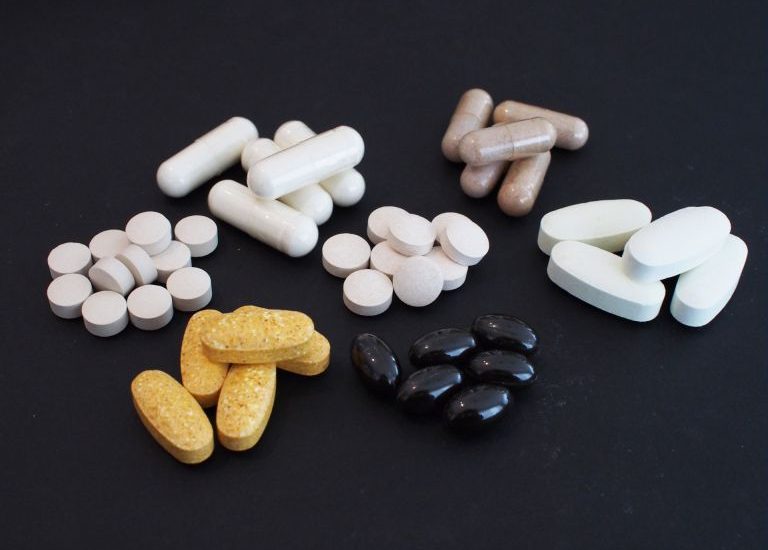

日常生活で取り入れる健康法を学び、心と体を充実させるライフスタイルを実現しましょう!